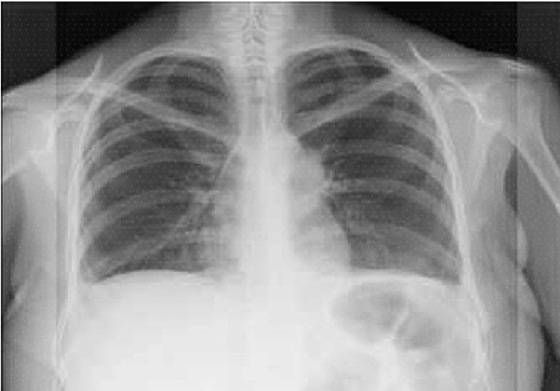

La paciente fue enviada 5 meses después a gastroenterología para descartar cáncer gástrico. Como parte del protocolo prequirúrgico para la realización de endoscopia se observó ensanchamiento mediastinal en la telerradiografía de tórax (Figura 1). El reporte histopatológico de la biopsia de estómago fue atrofia, engrosamiento de la capa muscular e infiltrado linfoplasmocitario, sin cambios compatibles con cáncer. En la tomografía toracoabdominal (Figura 2) se confirmó la tumoración en mediastino anterior. Fue sometida a toracotomía, donde se identificó un tumor mediastinal anterior de 8 a 10 cm, clasificado como timoma B1, con invasión a pericardio parietal y rama pulmonar izquierda.

Figura 1 Telerradiografía de tórax. Ensachamiento mediastinal como hallazgo para evaluación preoperatoria.